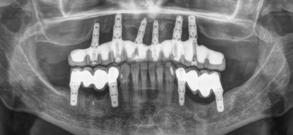

Retratamiento de un caso de periimplantitis de forma mínimamente invasiva. Extracción atraumática y confección de prótesis fija implantosoportada con carga inmediata. A propósito de un caso.

Retratamiento de un caso de periimplantitis

de forma mínimamente invasiva. Extracción atraumática y confección de prótesis fija implantosoportada con carga inmediata. A propósito de un caso

Dentista y Paciente 56 investigación clínica